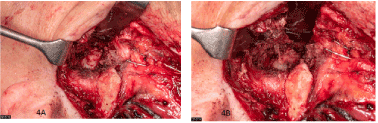

The TMJ was exposed through a preauricular approach and a temporary osteotomy of the zygomatic arch was conducted for better access. After blunt preparation through the pterygoid muscle the lesion presented as a fibrous mass of approximately 2 cm diameter with adhesion to the TMJ joint capsule. A capsule surrounding the lesion was not present (Figure 4a-b). The lesion was excised, therefore it had to be sharply dissected from the joint capsule. The zygomatic arch was repositioned and retained through an osteosynthesis plate. Postoperative facial motor function was uncompromised.

Figure 4. Intraoperative presentation of a fibrous lesion adjacent to the capsule of the temporomandibular joint